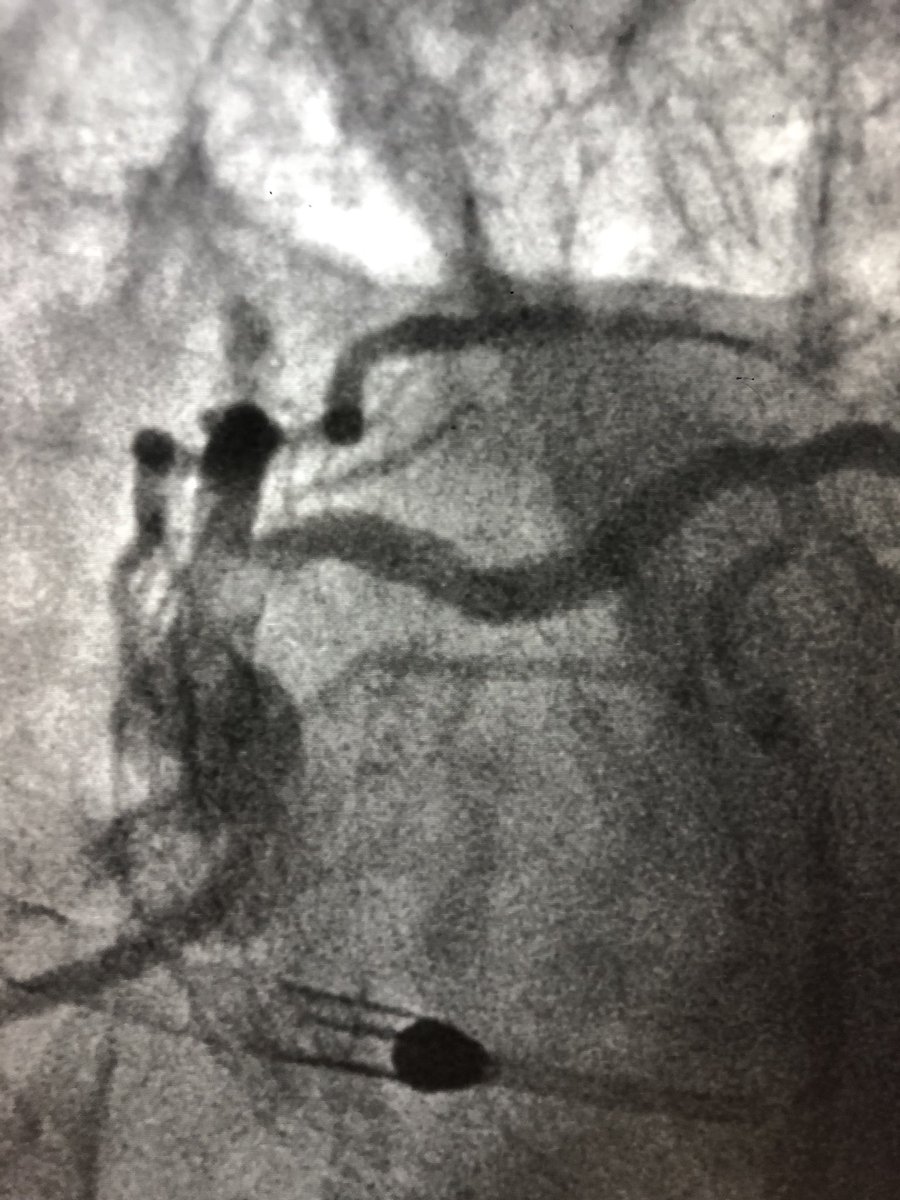

72 y/o WM with AS and LM/MV CAD. Complex bilateral iliac disease. #PercAx for Impella CP. Right ulnar access for DK crush for LM disease with left #radialfirst access for management of left axillary artery. Big thanks to @DrAmirKaki for showing me how.

matheenkhuddus's tweet image. 72 y/o WM with AS and LM/MV CAD. Complex bilateral iliac disease. #PercAx for Impella CP. Right ulnar access for DK crush for LM disease with left #radialfirst access for management of left axillary artery. Big thanks to @DrAmirKaki for showing me how.